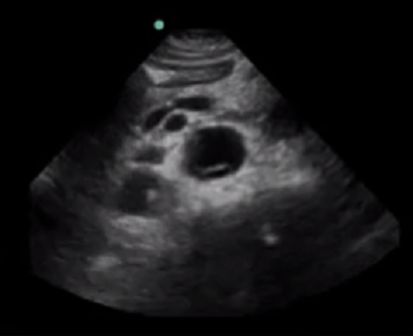

RUSH Aortic Dissection Image